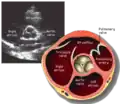

A transthoracic echocardiogram (TTE) is the most common type of echocardiogram, which is a still or moving image of the internal parts of the heart using ultrasound. In this case, the probe (or ultrasonic transducer) is placed on the chest or abdomen of the subject to get various views of the heart. It is used as a non-invasive assessment of the overall health of the heart, including a patient's heart valves and degree of heart muscle contraction (an indicator of the ejection fraction). The images are displayed on a monitor for real-time viewing and then recorded.

A TTE is a clinical tool to evaluate the structure and function of the heart. All four chambers and all four valves can be assessed by TTE, but the quality and visibility of these structures varies from person to person. Other structures visible on TTE include the aorta, the pericardium, pleural effusions, ascites, and inferior vena cava. It can be used to diagnose a heart attack, enlargement/hypertrophy of the heart, infiltration of the heart from an abnormal substance (e.g. amyloidosis). Weakness of the heart, and cardiac tumors. With advanced measurements of the movement of the tissue with time (Tissue Doppler), it can measure diastolic function, fluid status,[1] and ventricular dyssynchrony.

This view is obtained in the same window as the parasternal long, but with the probe rotated 90°. In this view, the aortic valve is seen in cross-section with the right ventricular inflow & outflow tracts visible with the tricuspid valve as well. Pulmonary valve is not visible in this view. Both the right and left atria are visible.

- Aortic valve in short-axis

- Aortic valve dysfunction, aortic sclerosis/stenosis

- Tricuspid valve in long-axis

- Pulmonary valve in long-axis

- Right ventricle, including inflow and outflow tracts

- Left ventricle in short-axis